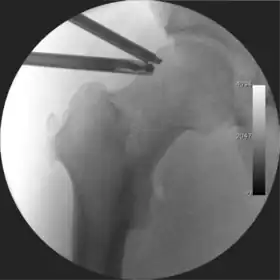

![]() Intraoperative fluoroscopic image during an arthroscopic resection of a cam lesion of the femur. The upper instrument is the arthroscope (viewing device), while the lower is the high-speed burr used for reshaping the bone. |

Figure 3. Fluoroscopic picture showing a mild amount of distraction of the hip before insertion of any instruments

The procedure is performed with the patient asleep (general anaesthetic) or under spinal anaesthesia. There are two widely used methods, one with the patient on their back (supine) and the other on their side (lateral decubitus). Which is used is down to the surgeon's preference. To gain access to the central compartment of the hip joint (between the ball and socket), traction is applied to the affected leg after placing the foot into a special boot. (See fig. 2) There is specifically designed equipment for this, although some surgeons use a 'traction table', initially designed to help in the operative fixation of broken thigh and lower leg bones. The amount of traction (or pull) needed is assessed with the help of fluoroscopy (low-dose portable x-ray). (See fig. 3) It is usually not possible to distract the ball from the socket with traction alone by more than a few millimetres. Once the surgeon is happy that they will be able to gain access to the hip joint (i.e. the ball will distract from the socket by a small amount), the patient is then painted with antiseptic and the surgical drapes applied.

The next step is to insert a fine needle under x-ray guidance into the hip joint. This breaks the 'suction seal' of the joint and allows further distraction if necessary (see fig 4). The surgeon wishes to see the ball move out the socket by approximately 1 cm, so that access to the hip joint can be achieved with minimal risk of damage to the joint surfaces. Most surgeons will inject fluid into the joint at this stage, again to ensure that there is enough space between the ball and socket for safe instrument access. This needle is then removed. The next step is placement of the 'portals', or the small holes made to pass instruments into the joint. This is achieved by again passing a fresh hollow needle into the joint under x-ray control, usually in a slightly different position. The reason for this is so the surgeon can ensure that the needle, and subsequent cannulae do not penetrate and damage the acetabular labrum or cartilage joint surfaces (see fig. 5). Again, surgeons will have their own preferences as to their preferred placement. Through this hollow needle, a long thin flexible guide wire is passed into the joint, and the needle is removed over it, leaving the guide wire in situ. A small cut in the skin is made around the wire, to allow for larger cannulae to be placed over the wire through the portal. The wire therefore guides the larger cannulae into the joint. The most common external diameters of cannulae used are between 4.5 and 5.5 mm. Once the surgeon is satisfied that the cannula is in the correct position, by a combination of feel and x-ray guidance, the guide wire can be withdrawn. Once the first portal is correctly placed, any further portals may be created once the camera is in position, to ensure that they are placed with minimal risk to the joint surfaces. This process can be repeated to gain as many points of entry to the hip joint as the surgeon requires, normally between two and four. Certain of these entry points will be used for the viewing arthroscope and others for operating instruments.